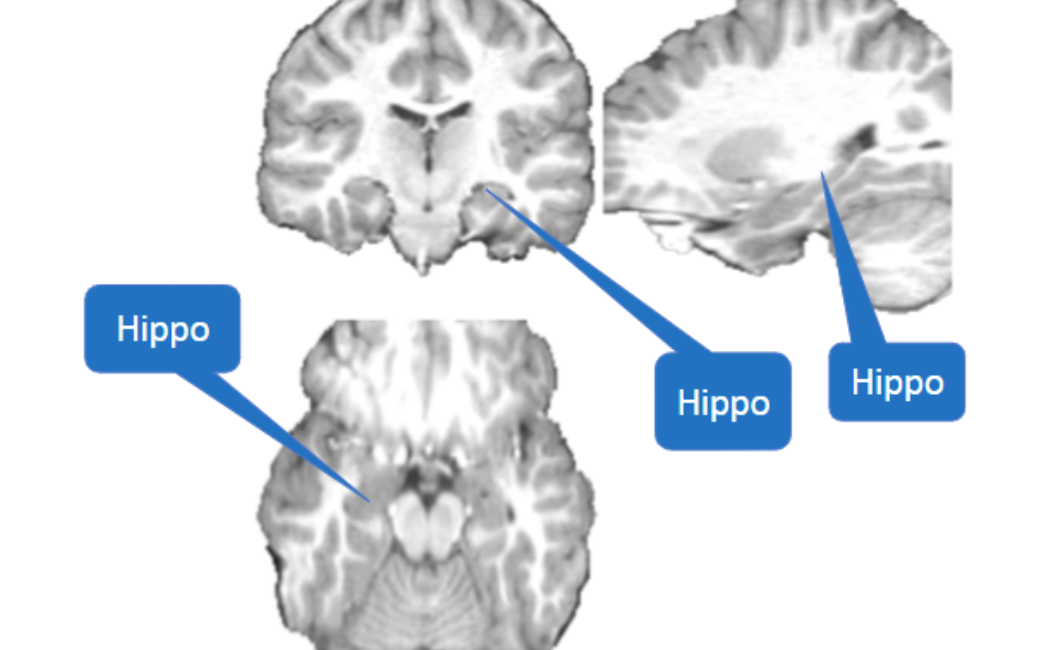

Hippocampus Location

Hint from class?

Gray banana = hippocampus

Hippocampal proper

The C-shaped structure of the hippocampus